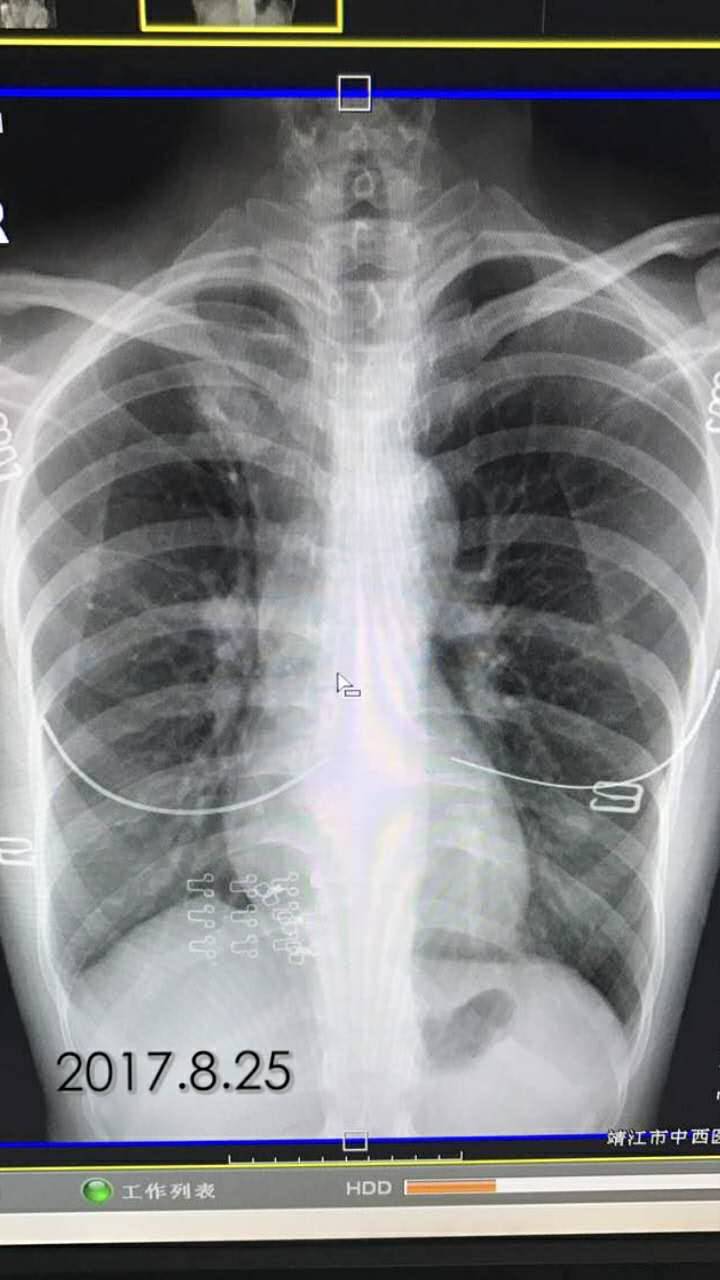

2017.8.25

举报

2017-10-31 10:37:00 有用(0)

回复(0)